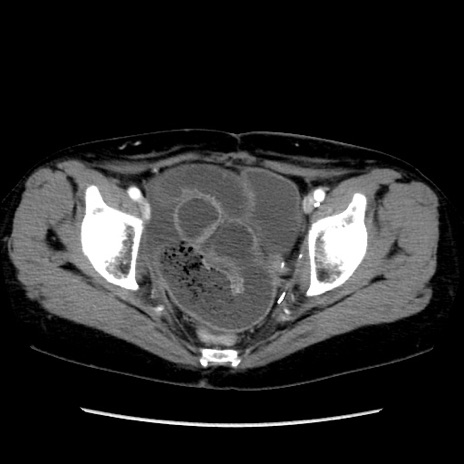

症例32(横断像)

【症例】40歳代 女性

【主訴】上腹部痛、嘔気・嘔吐

【現病歴】約9時間前頃から急に上腹部痛、嘔気、嘔吐が出現。改善しないため救急要請。

【既往歴】子宮頚癌(広汎子宮全摘術、放射線療法)、腸閉塞